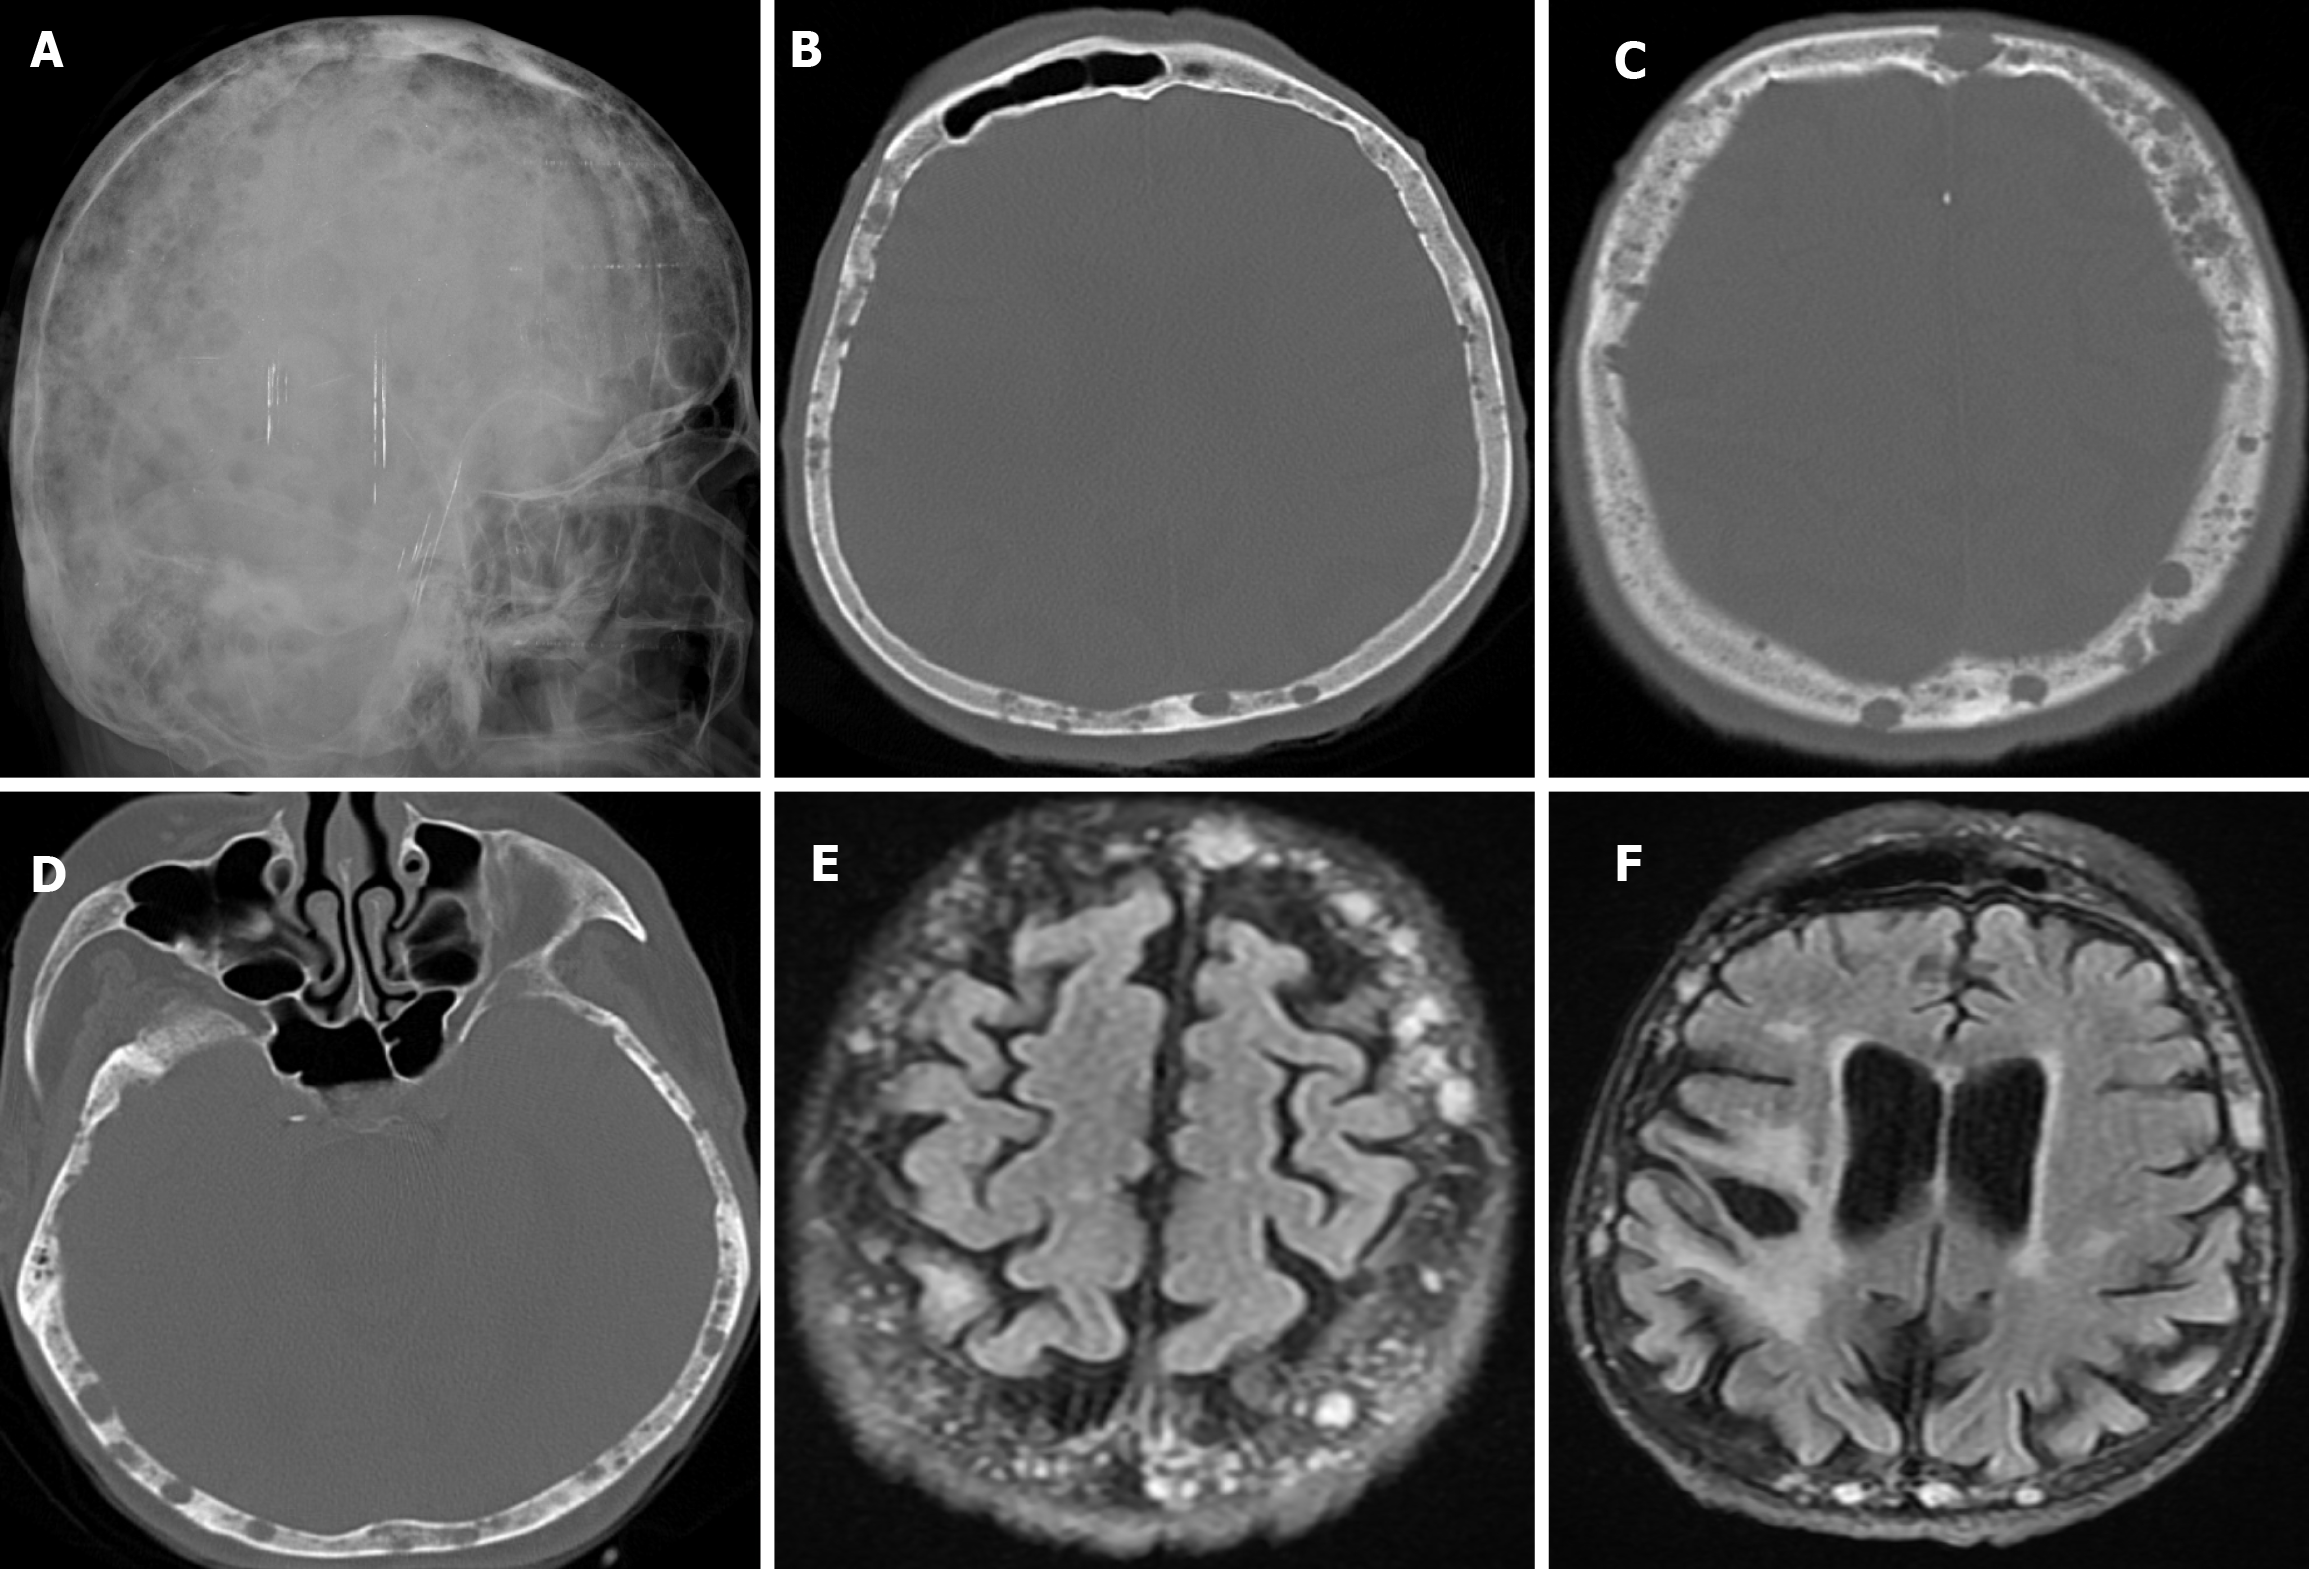

Skeletal changes in chronic anemia are due to ineffective erythropoiesis as a result of impaired haemoglobin synthesis, peripheral destruction of erythrocytes and consequently reduced erythrocyte lifespan. Radiography show massive hyperplasia of the bone marrow associated with hyperactivity of the bone marrow in response to anemia. The hair-on-end sign is seen on plain radiography of the skull, CT and MRI as long, thin vertical lines of calcified spicules perpendicular to the bone surface, appearing as upright hairs. The hair-on-end appearance of the skull is a characteristic feature of chronic haemolysis, usually seen in patients with thalassaemia (Figure 14) and sickle cell disease. The incidence of hair-on-end appearance in patients with thalassaemia is 8.3%. Although rare, the hair-on-end sign has also been described in iron deficiency anemia, sickle cell disease, cyanotic congenital heart disease, hematological malignancies and nutritional deficiencies. The appearance of these projections indicates excessive medullary erythropoiesis in patients and is rare before the age of 5 years. As the bone lesions are explained by the relationship between proliferating bone marrow and bone cortex, only hypertransfusion initiated early in life will prevent the development of the abnormality[55].

Renal osteodystrophy refers to abnormalities of bone morphology in chronic renal failure. Phosphate retention and reduced vitamin D conversion lead to hypocalcemia, which stimulates parathyroid hormone production and causes bone resorption. Therefore, factors such as secondary hyperparathyroidism and abnormal vitamin D metabolism contribute to renal osteodystrophy. Some imaging features of renal osteodystrophy overlap with those of hyperparathyroidism and rickets or osteomalacia. Skeletal findings in renal osteodystrophy include generalised demineralization, trabecular thickening, subperiosteal resorption, cortical thinning, bone cysts and pathological fractures. A diffuse increase in bone density is seen on imaging in patients with chronic renal failure. This finding is more common in the axial skeleton, which has more trabecular bone than cortical bone. Despite the increased radiodensity, the bone is structurally weak and more susceptible to stress fractures. This diffuse osteosclerosis is thought to be due to the anabolic effect of parathyroid hormone. The salt-and-pepper appearance in renal osteodystrophy (Figure 15) results from diffuse bone thickening with loss of distinction between the inner and outer tables of the skull and granular deossification due to low-density lytic foci scattered within the normal bone[9,56].

Intraosseous venous malformations are rare, benign, slow-growing lesions that account for 2%-10% of calvarial tumors and 0.2% of all bone neoplasms. The skull is the second most common site after the spine. In the calvarium, these pathologies tend to be confined to a single bone, most commonly the frontal and parietal bones. These lesions are more common in the 2nd to 4th decades of life and in women. Most of these lesions are small and present as palpable swellings on the scalp or as lesions found incidentally on radiological examination. They may be associated with headaches, rarely neurological symptoms, and may initially be extremely large. Calvarial venous malformations are thought to result from aberrant differentiation of intradiploic veins between the inner and outer table of the bone[67].

On plain radiography, calvarial intraosseous venous malformations appear as well-defined round or oval lytic lesions. As the lesion consists of malformed venous channels within the bone trabeculae, calvarial venous malformations occur primarily in the diploic space, with an expansile appearance and thinning of the overlying cortex. Although not entirely specific, thick trabeculations extending from the center of the lesion to the periphery give a classic mottled, spiculated, honeycomb, spoke or sunburst appearance. On CT, it appears as a well-circumscribed, intradiploic, expansile lytic lesion with trabeculations and spicules (Figure 22). There is a sharp demarcation between the lesion and normal bone, and peripheral sclerosis is seen in 30% of cases. In most cases, the outer table of the skull is widened with the preservation of the inner table. Variable bone density is thought to reflect osteoblastic activity due to chronic and recurrent hemorrhage. MRI findings are variable, and on T1-weighted imaging some lesions have high signals from thrombus or fat, which a fat-suppressed technique can distinguish. On T2-weighted images, lesions have a markedly hyperintense signal, reflecting slow-flowing blood or subacute thrombus. A larger lesion may show more hypointense foci due to thickened trabeculae. After paramagnetic contrast administration, focal areas of enhancement in the early phase and a diffuse enhancement pattern in the late phase are shown. Dural enhancement, similar to meningioma, is rarely seen[7,49,66].